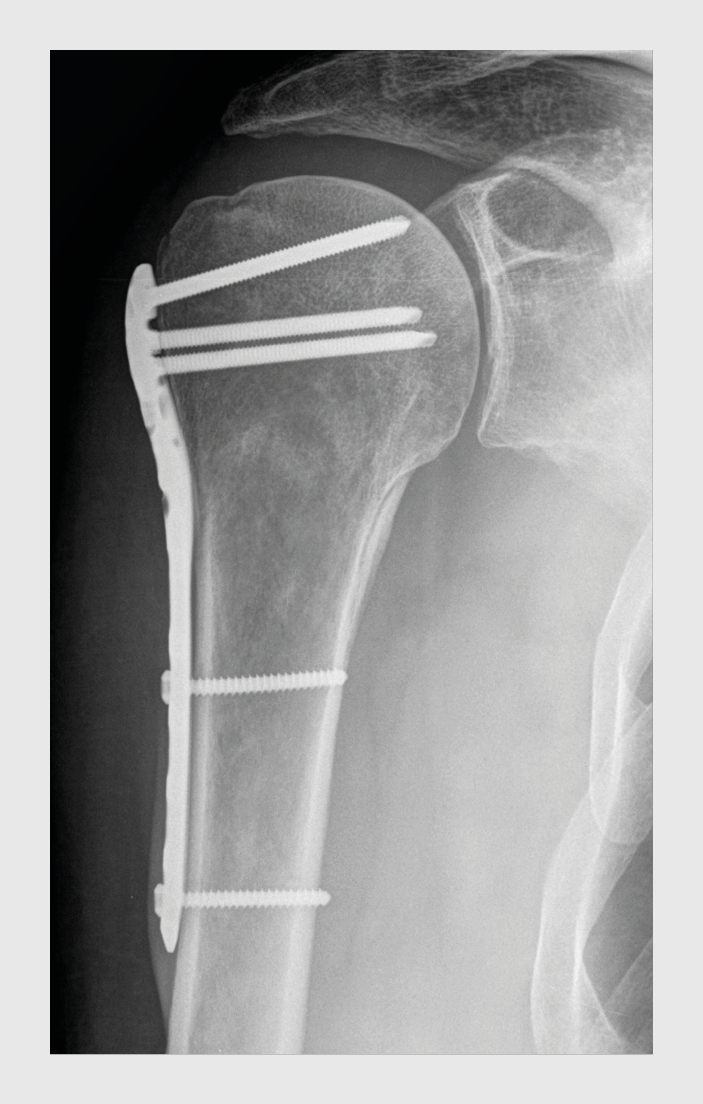

Figuur 3

Figuur 3 |

Röntgenfoto van de rechter schouder van de patiënt in figuur 1a, 2 dagen na osteosynthese met een Philos-plaat.